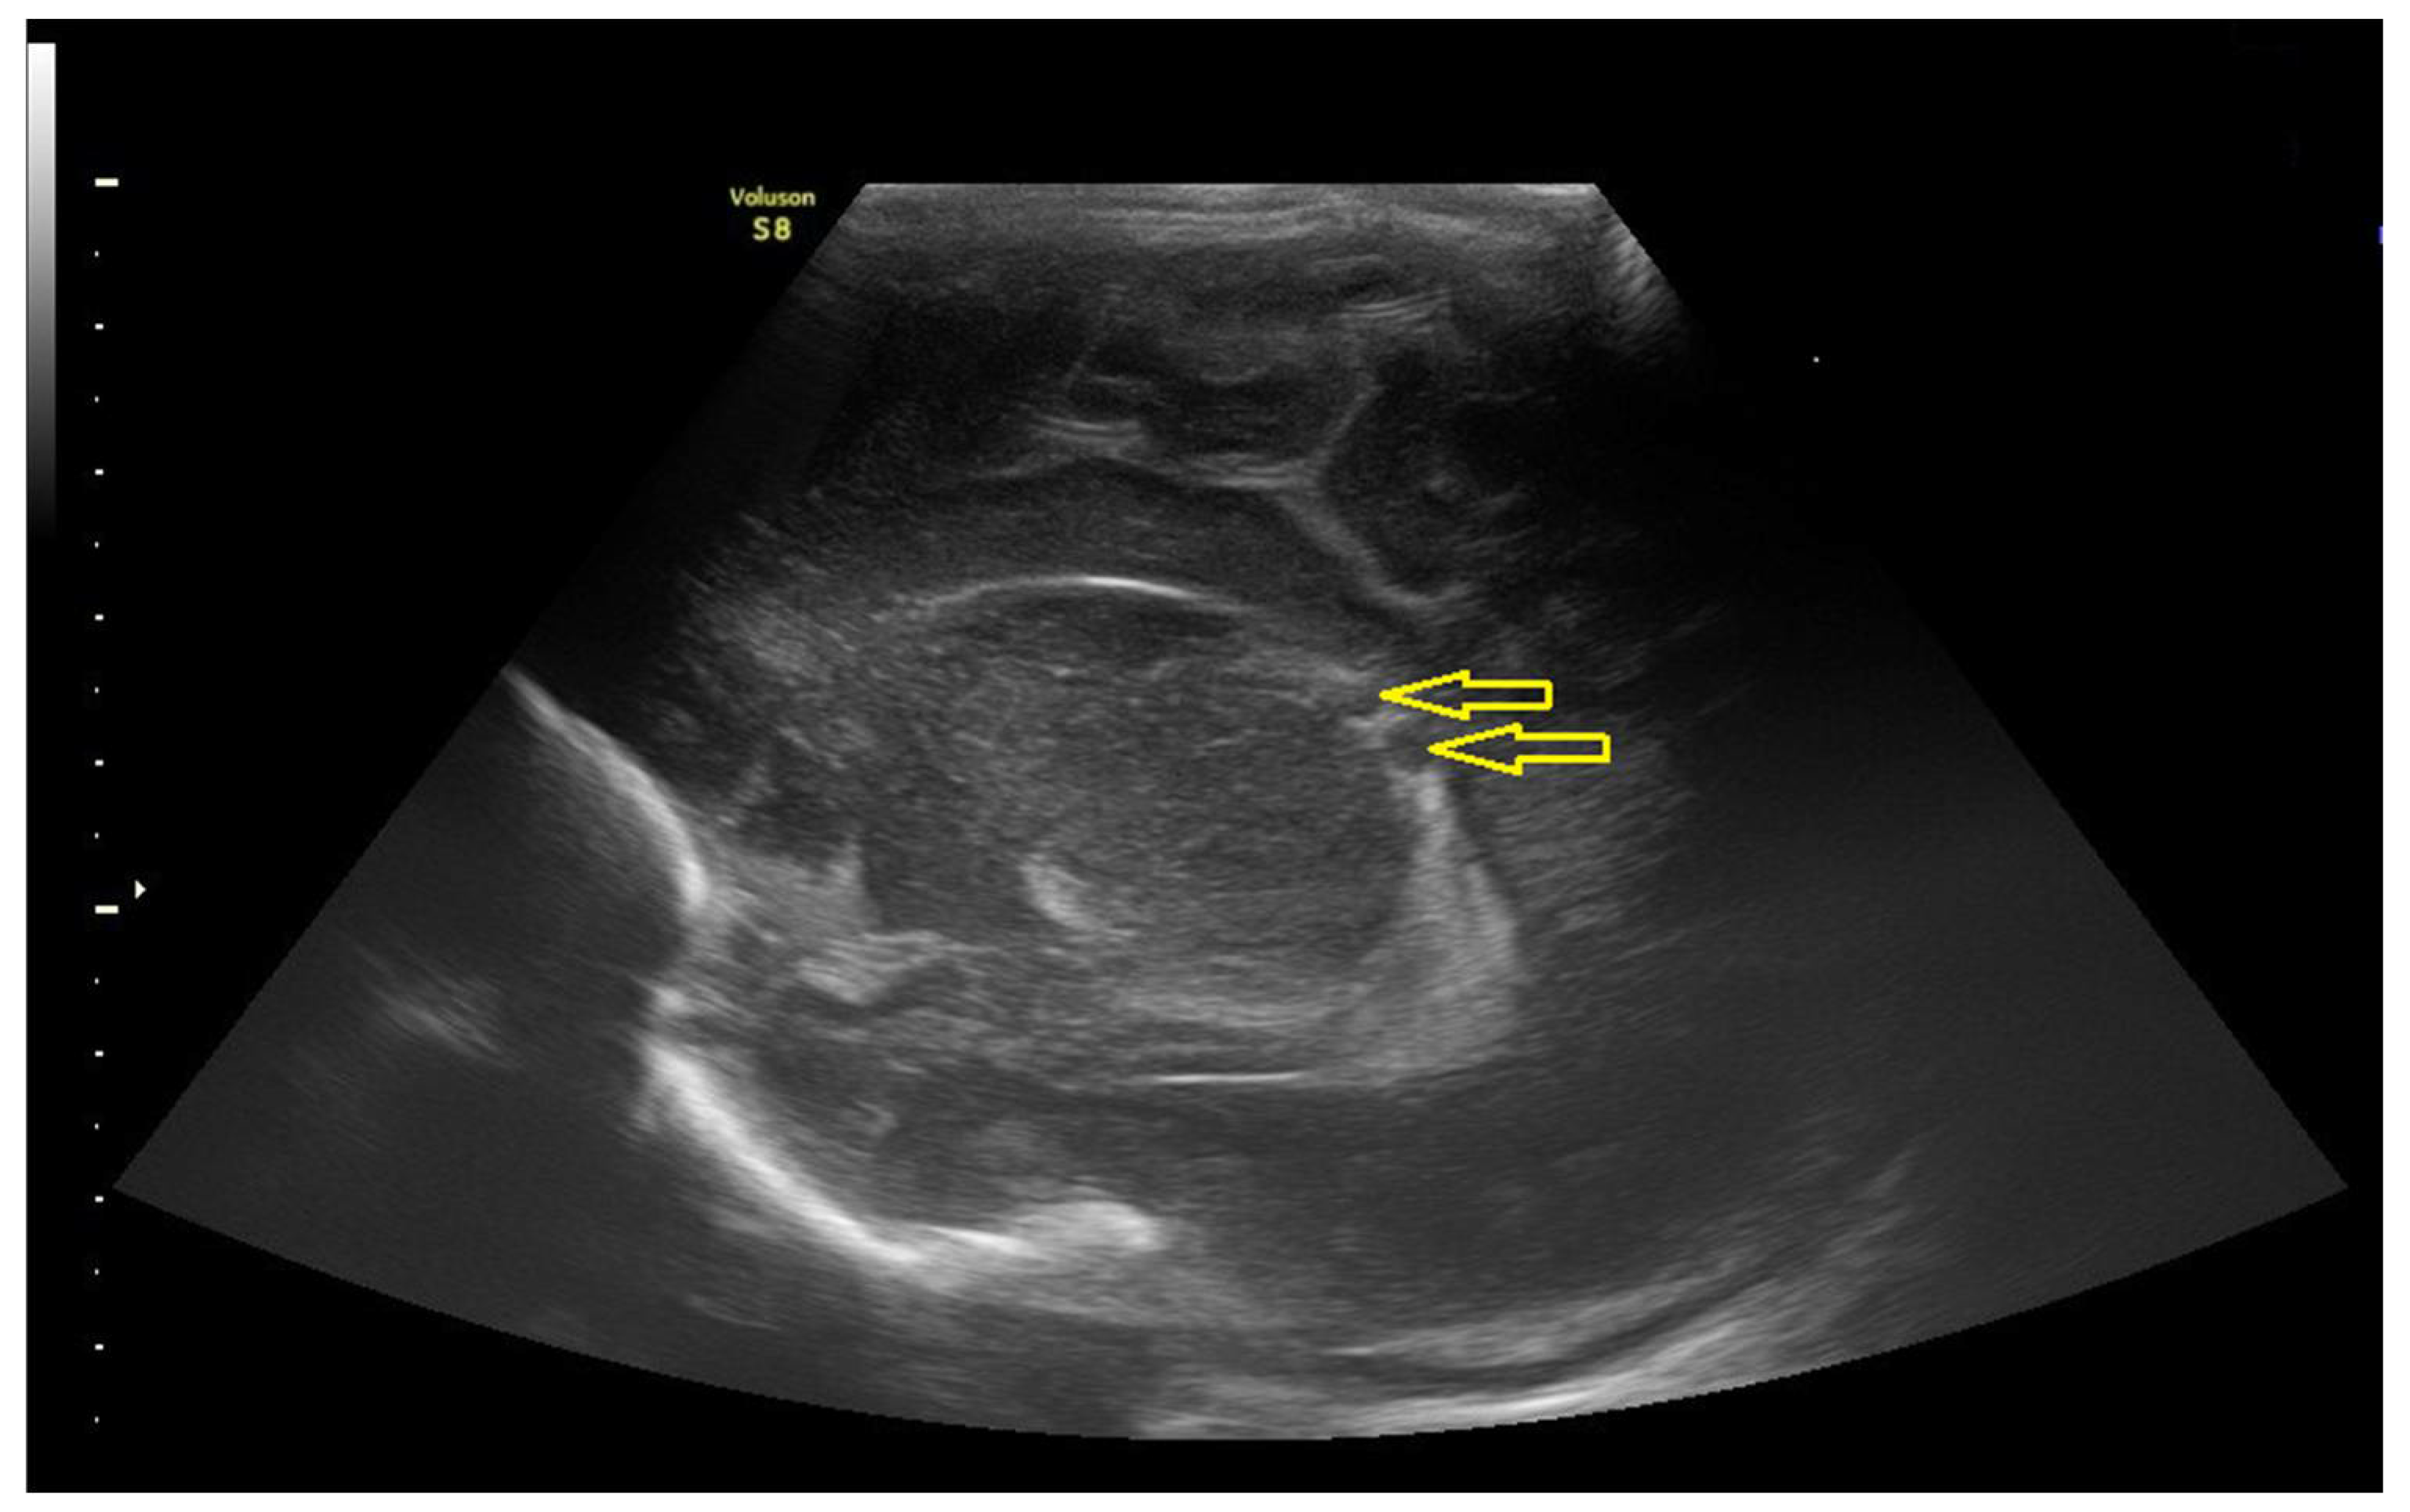

3.1.2. Data of the Instrumental Methods of Examination